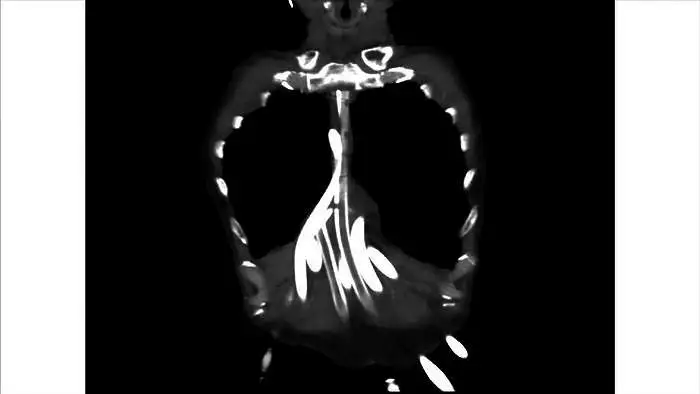

13.

这是他的电脑断层扫描,理论上,胸腔里应该有一颗心脏,可是现在没有心脏,只看到一些管子。